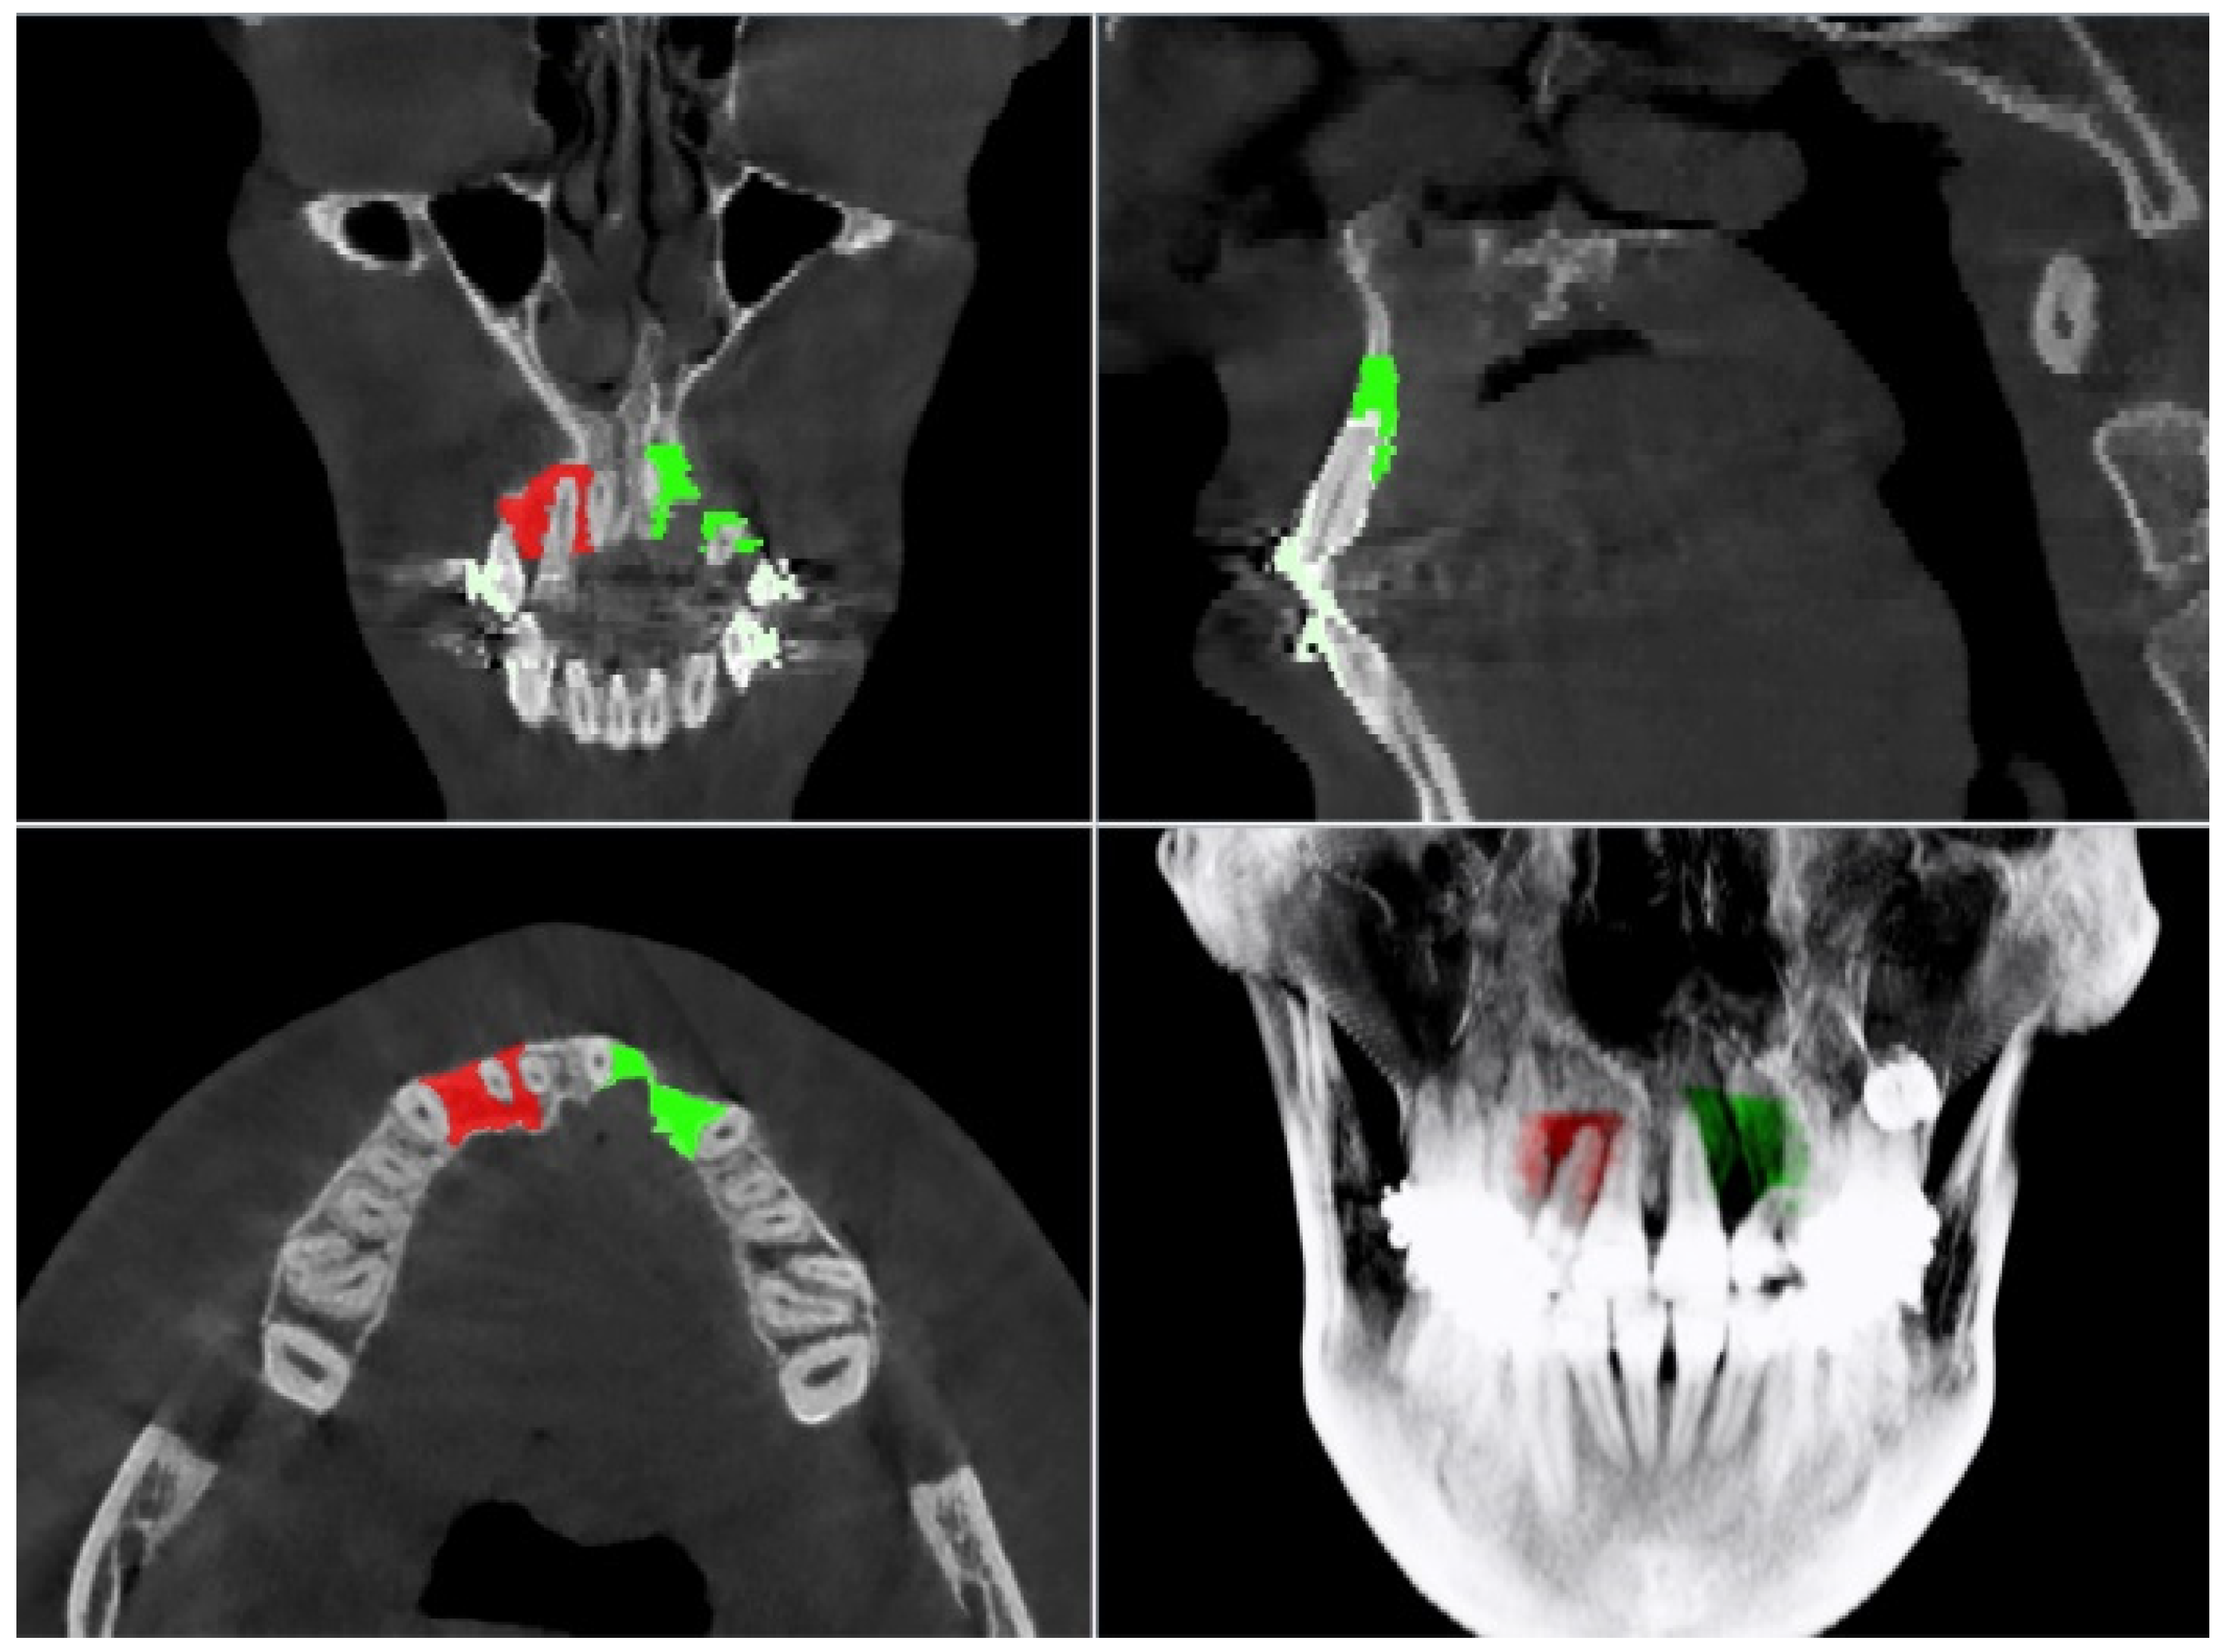

2.3. Computed Tomography (CT) Evaluation